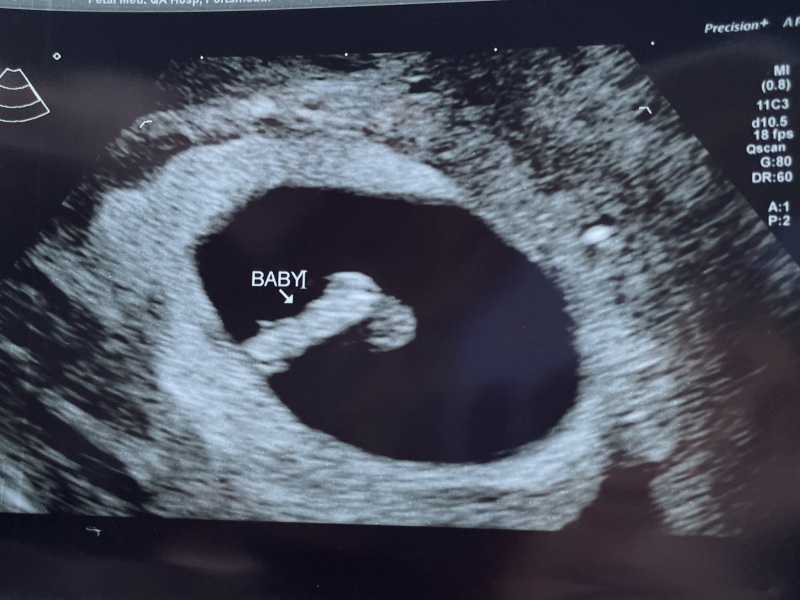

Scan done and everything is great! Little beansprout is where they should be and had a heartbeat 🥰 measuring 7 weeks (I’m 6+6 so about right). I’m so relieved.

Due September 2024

Its also nice to know that your own counting is on point with the picture

Lovely scan pic @MrsB2019x 💕 good luck with yours later @Xur

Beautiful scan pic @MrsB2019x you must feel so reassured!